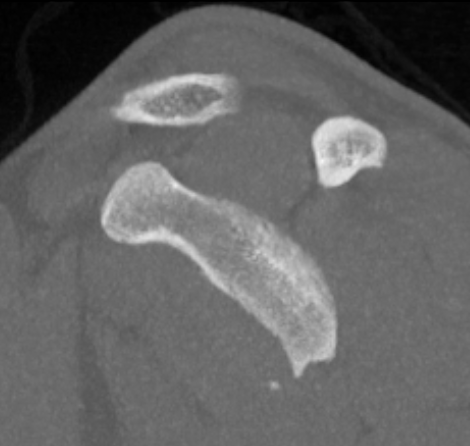

Case 1: Failed Latarjet